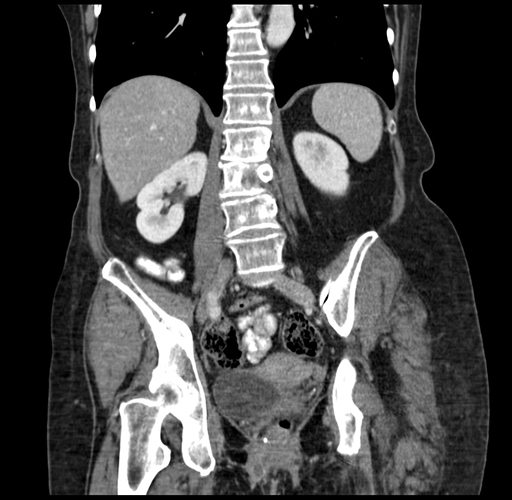

Pre-Chemo: Axial Venous

Pre-Chemo: Coronal Venous